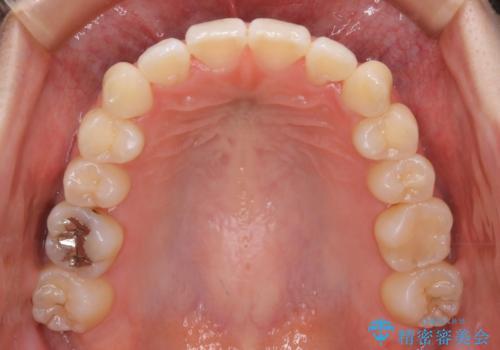

矯正装置の希望がインビザラインだったため、マイクロインプラントを併用し、奥歯から順に遠心移動をかけていくことにより非抜歯でも主訴のガタつきを治すことができました。

術前・術後の笑った時の歯の見え方の変化にも注目してみてください!

マウスピースとマイクロインプラントを組み合わせることで、抜歯をしなくても歯並びを治すためのスペースを作ることができます。奥歯から順に移動させていくので前歯に変化が出るまでには時間がかかりますが、その分健康な歯を抜歯することなく理想的な歯並びを手に入れることができます。